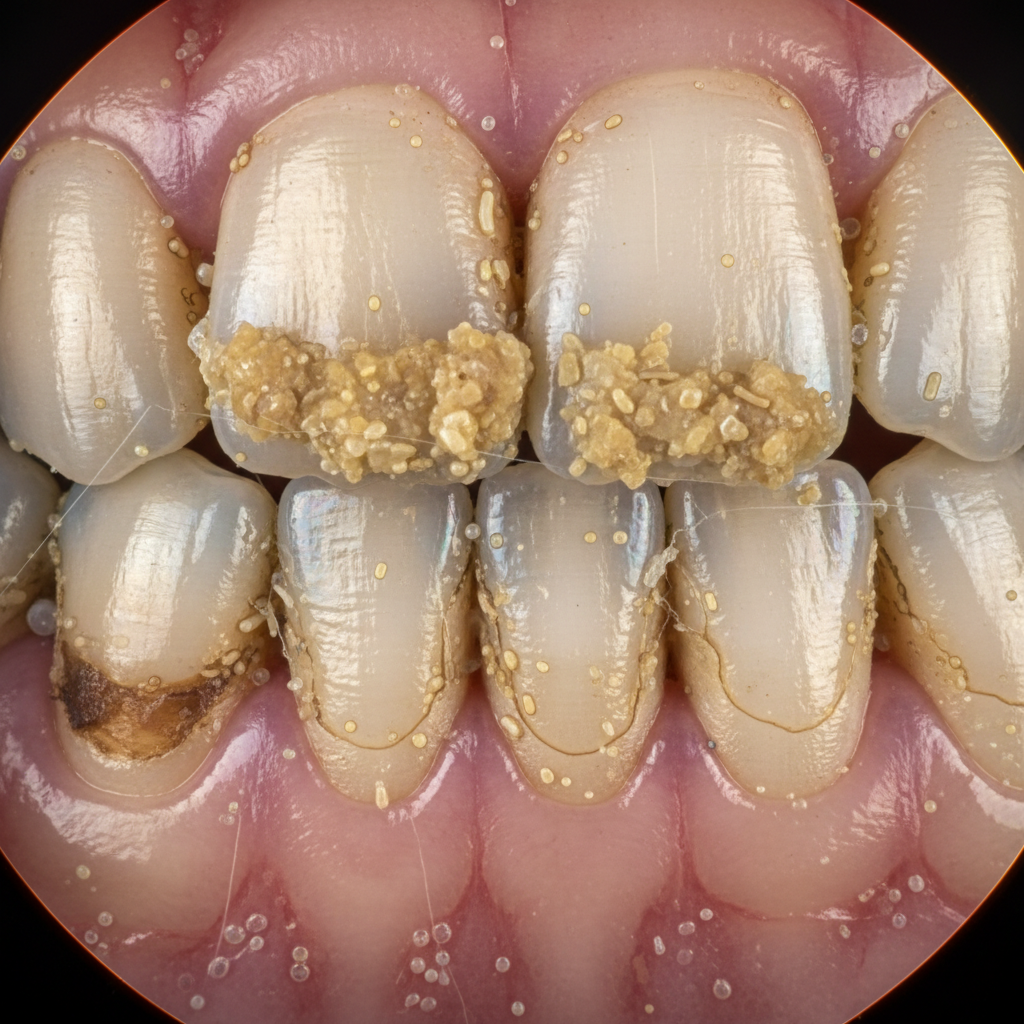

Co się dzieje w twojej jamie ustnej — anatomia problemu

Kamień nazębny powstaje z płytki bakteryjnej, która mineralizuje się pod wpływem śliny, tworząc twarde złogi na powierzchni zębów – zwłaszcza w pobliżu ujść ślinianek. Te kryjówki dla bakterii są praktycznie nieusuwalne zwykłą szczoteczką. Z czasem złogi zaczynają rosnąć „pod dziąsło”, tworząc idealne warunki dla rozwoju stanów zapalnych i destrukcji tkanek przyzębia. Złogi mogą być żółte, brunatne, a nawet czarne – wszystko zależy od diety, nałogów i higieny. Proces ten napędza błędne koło: im więcej kamienia, tym więcej bakterii – i tym trudniej go usunąć bez pomocy specjalisty.